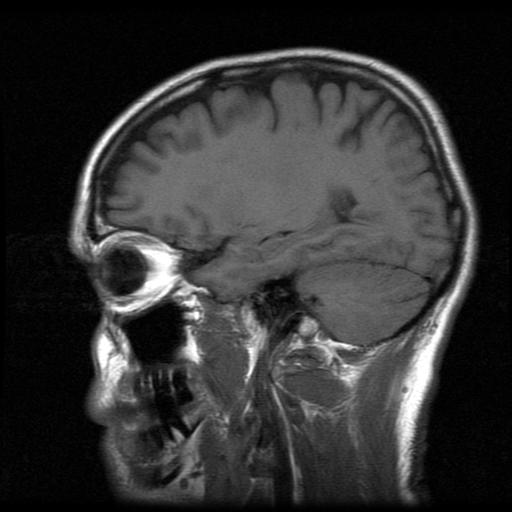

Other researchers are testing deep brain stimulation to control depression and obsessive-compulsive disorder resistant to other therapies. The surgery involves drilling holes into the skull to implant wires into the fornix on either side of the brain.

The fornix is a brain pathway instrumental in bringing information to the hippocampus, the portion of the brain where learning begins and memories are made, and where the earliest symptoms of Alzheimer’s appear to arise. The wires are attached to a pacemaker-like device, the “stimulator,” which generates tiny electrical impulses into the brain 130 times a second. The patients don’t feel the current, Rosenberg says.